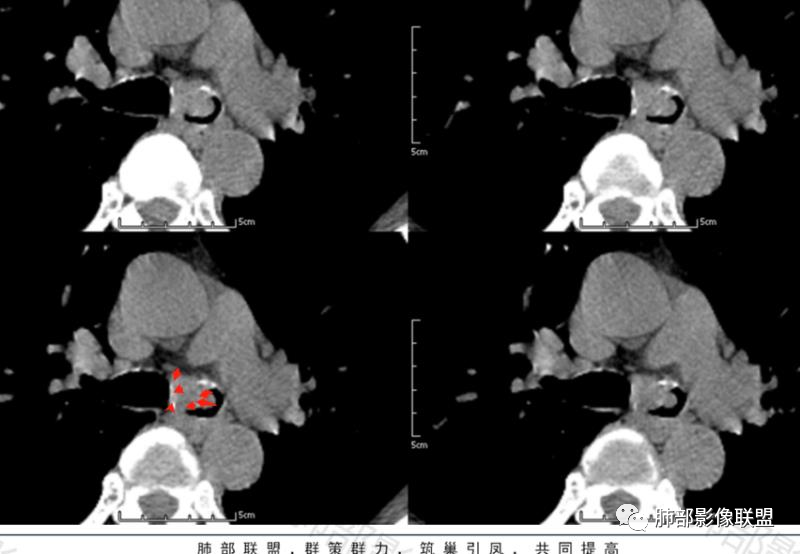

晨读57岁的男性病人,病史一周,以咳嗽咳痰痰中带血为主要表现, CT扫描与支气管分叉偏左侧支气管的位置上见分叶状的一个结节影,并局部凸向管腔内,支气管管腔明显的变窄, 病灶以实性为主,周围斑点状的钙化,生长支气管内外侧壁,可见“冰山征”,增强扫描比较明显的强化,肿块未见坏死,周围无明显肿大淋巴结。考虑支气管来源的占位。类癌?鳞状细胞癌?鉴别:支气管息肉?硬化性血管瘤?

1、病灶腔内为主

2、局部软骨不连续,壁外有增厚,提示局部软骨破坏,壁外有病灶

3、明显强化

定位:左主支气管

定性:考虑低度恶性肿瘤性病变